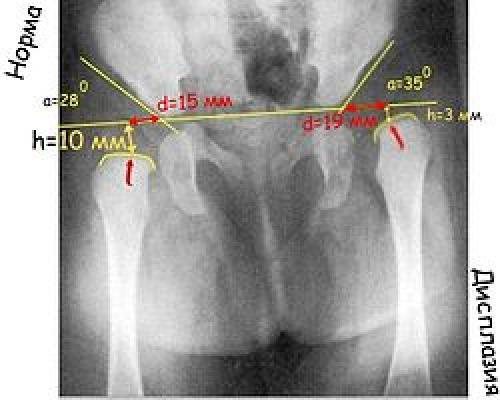

Ацетабулярный угол, или ацетабулярный индекс — метод измерения деформации тазобедренного сустава, который характеризует угол наклона верхней части вертлужной впадины. Применяется при рентгенологическом обследовании.

Нормальный ацетабулярный индекс у новорожденного до года составляет не больше 28° . При достижении ребенком одного года и более этот показатель снижается до 22°.

Прежде всего проводят вертикальную срединную линию, она проходит через середину крестца. Проводят горизонтальную линию через У-образные хрящи, через нижние точки подвздошной кости (линия Хильгенрейнера). Через наружно верхний край, перпендикулярно горизонтальной линии проводят линию Перкина . Часто бывает, что на стороне поражения невозможно определить верхний край вертлужной впадины. В этих случаях пользуются методом Рейнберга: симметрично, на таком же расстоянии от срединной линии проводят вертикальную линию (перпендикулярно горизонтальной). Она и будет обозначать невидимый на рентгенограмме верхнелатеральный край впадины. Через края вертлужной впадины проводят касательную линию до пересечения с горизонтальной линией Хильгенрейнера. Образованный угол называется «ацетабулярный угол», или угол наклона крыши вертлужной впадины.

Величина ацетабулярного угла в норме составляет менее 30° у новорождённых и около 20° у детей от 3 месяцев и старше.